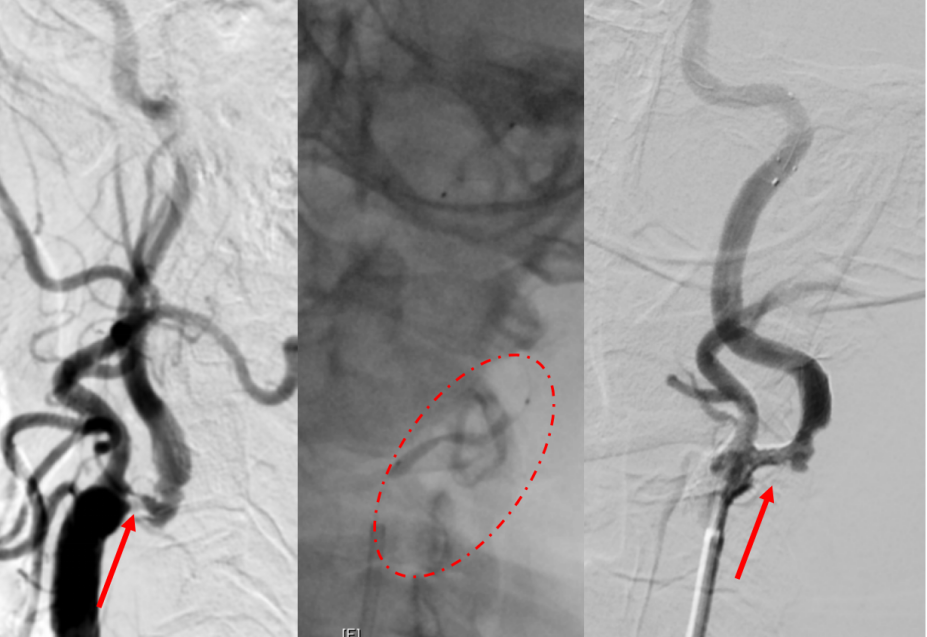

睡醒后发现脑梗 清华长庚绿色通道全时全力抢救